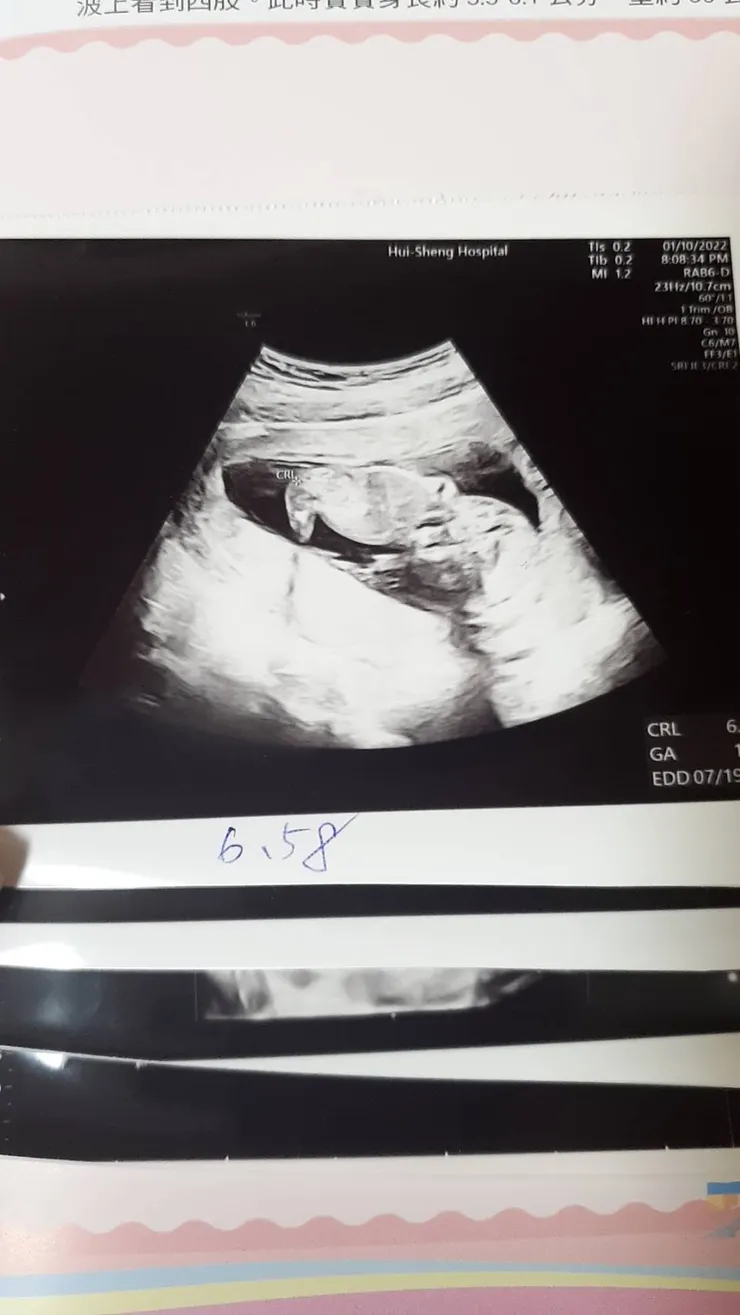

當我們從女人變成母親,這個過程並不只是一個新角色的開始,而是整個內在價值與生活習慣的重塑。 🔹孕期適應期:從知道懷孕的那一刻,開始意識到「自己的身體不再只屬於自己」,我們將面臨生理上、身材上、心理上的變化,同時也將自己生活上的重心都給了腹中胎兒;開始吃孕期營養品、開始研究產檢項目、開始做起胎教、開始準備嬰兒用品,任何與嬰兒相關的字眼都瞬間進入了眼簾。🔹新手媽媽期:迎接新生兒的到來,充滿喜悅的同時,也伴隨著焦慮、壓力、甚至自我懷疑,人生開始充滿了擔憂,哭鬧不睡覺擔心寶寶生病、睡得安穩沒聲音擔心沒了呼吸、吃得太少怕寶寶長不大、吃得太多又怕寶寶過於肥胖;生活中各種小事都能成為我們的隱憂。